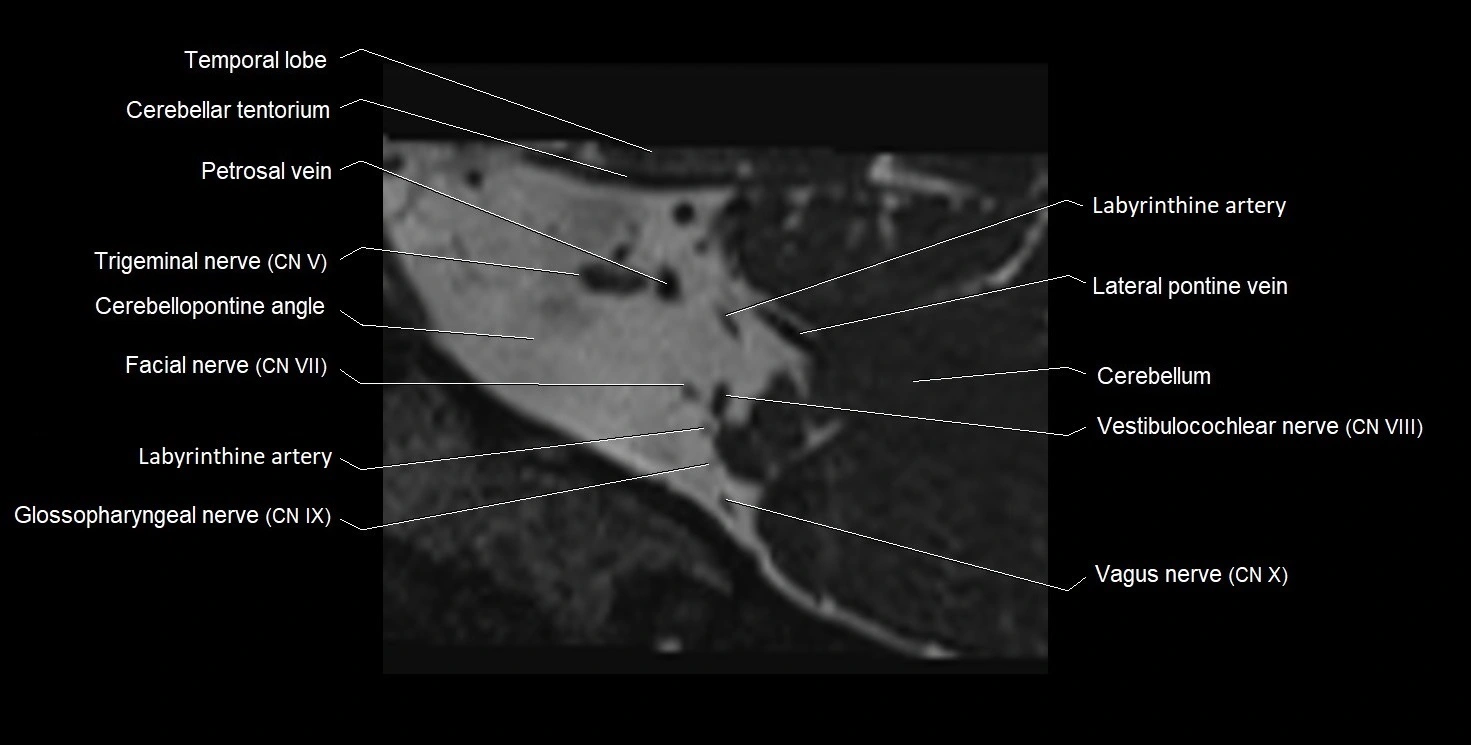

MRI images

image